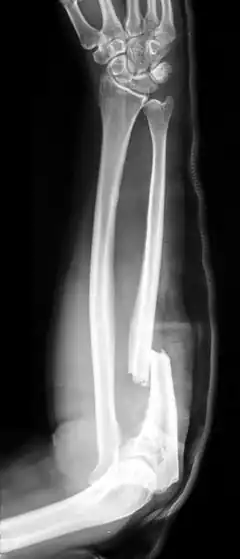

Radiographie d'une fracture de Monteggia

La fracture de Monteggia est une fracture osseuse de l'avant-bras sur l'os de l'ulna avec luxation de la tête du radius. Ce traumatisme est dénommé Monteggia en raison de l'étude médicale effectuée par le chirurgien et anatomiste italien Giovanni Battista Monteggia (1762-1815).